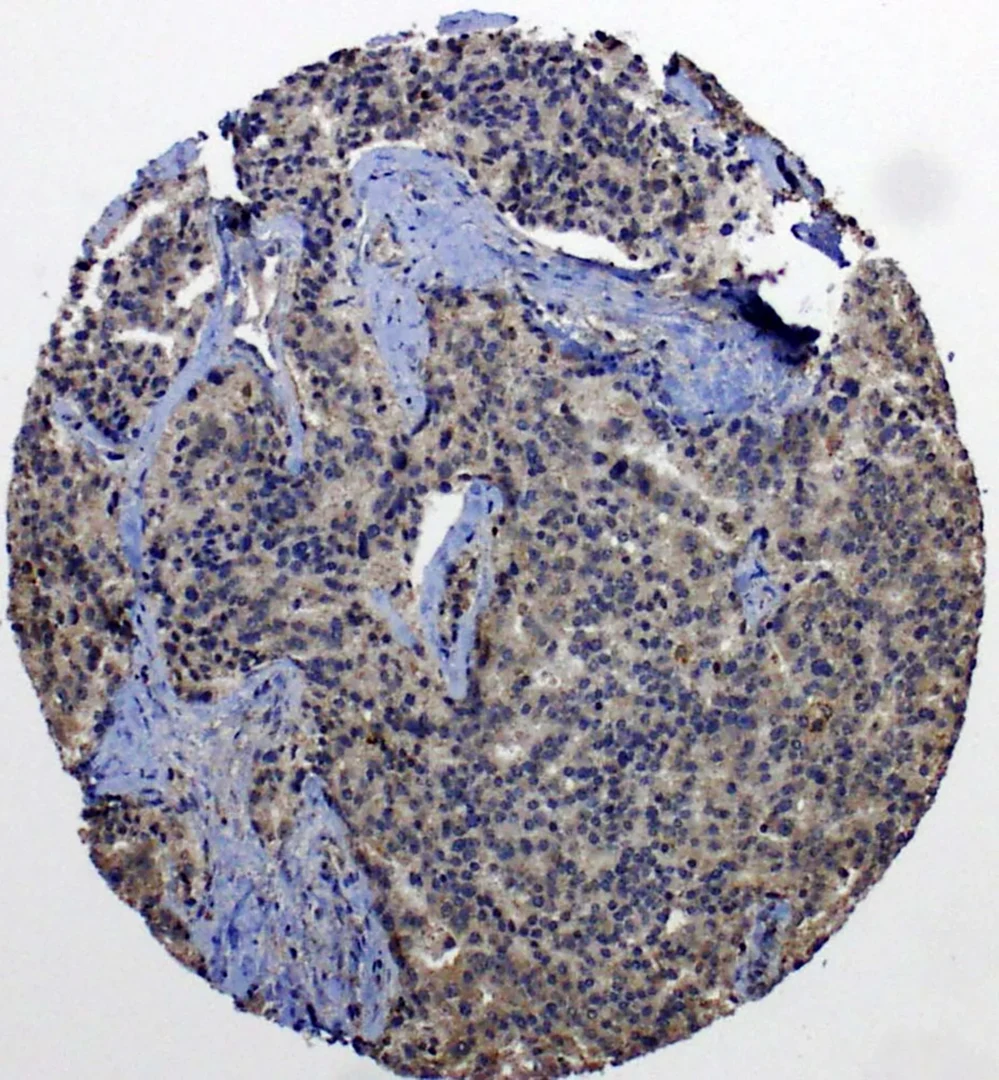

Auch hier erkennt man eine hohe Neuropilin-2-Expression

Auch hier erkennt man eine hohe Neuropilin-2-Expression - in den metastasierten Prostatakarzinomzellen (in braun). © Muderslab